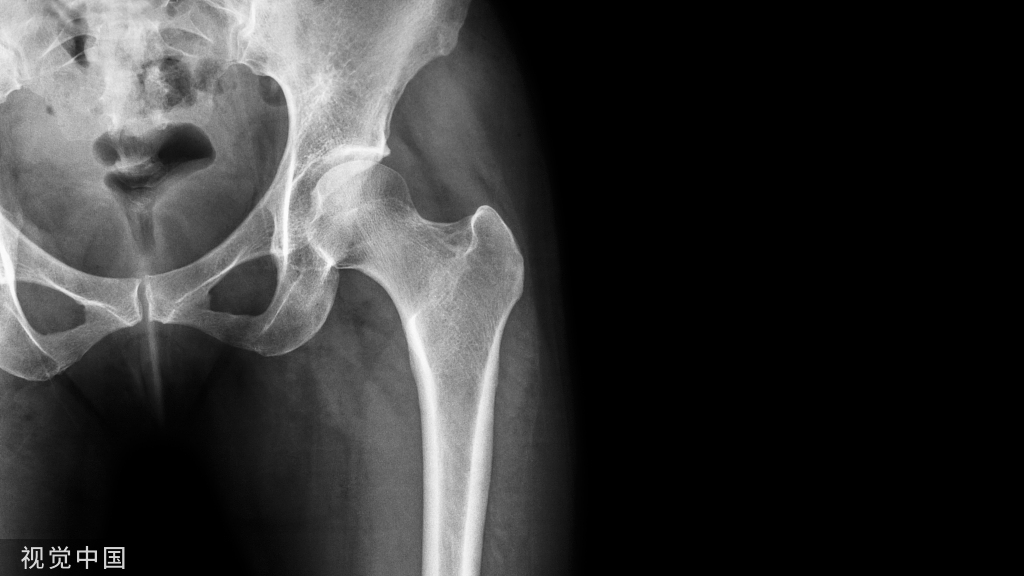

偏心距(Offset)股骨偏心距:股骨头中心到股骨纵轴的垂直距离外展肌的动力臂

髋关节的偏心距(Hip Offset)

-髋关节偏心距 ≠ 股骨偏心距

-关注髋臼(臼杯)偏心距acetabular or cup offset,AO